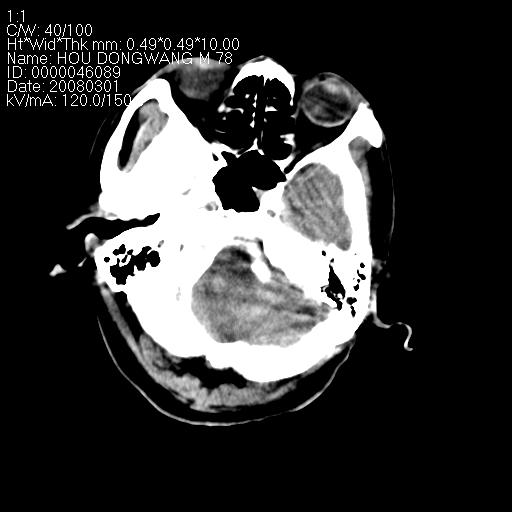

男,78岁。自诉两周前因右侧肢体障碍行ct检查,诊断为脑梗塞(患者ct片已丢失)治疗好转后出院。现因意不清12小时,又行ct检查。

结合病史考虑中性脑出血并脑疝形成,血肿破入下腔及脑室.

结合病史考虑左侧额颞顶叶出血性脑梗塞。